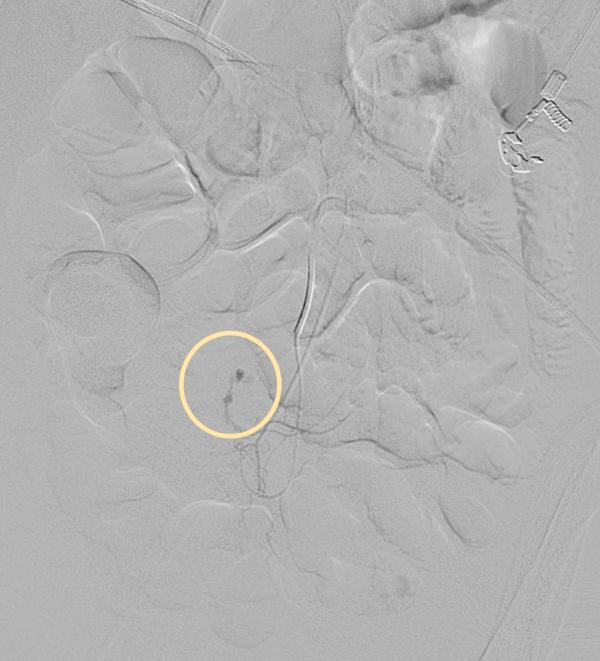

We describe the successful treatment and outcome of a lady who initially presented with perforation of the colon at the rectosigmoid junction, for which she underwent resection and anastomosis. A few days later, she was noted to have persistent hematochezia, which was secondary to bleeding pseudoaneurysms at the rectosigmoid branches of the inferior mesenteric artery. She successfully underwent selective angioembolisation of these pseudoaneurysms with gelfoam. She did not suffer any complications from the procedure.

我们描述了一位女性患者的成功治疗过程及结果。该患者最初表现为直肠乙状结肠交界处结肠穿孔,为此接受了切除和吻合手术。几天后,发现她持续便血,这是由肠系膜下动脉直肠乙状结肠分支处的假性动脉瘤出血所致。她成功接受了这些假性动脉瘤的选择性明胶海绵血管栓塞术,且未出现该手术的任何并发症。